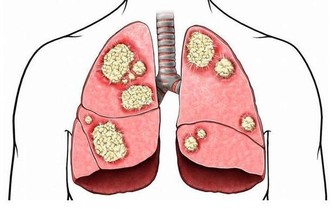

據報導,一位70歲老漢突然眼瞼下垂、噁心嘔吐,送進醫院後更是出現呼吸衰竭的情況,醫生確診為破傷風、感染中毒性休克和肺部感染等,被緊急轉入ICU搶救。

而引起這一切的原因竟然只是因為用牙籤剔牙的時候不小心損傷了牙齦!